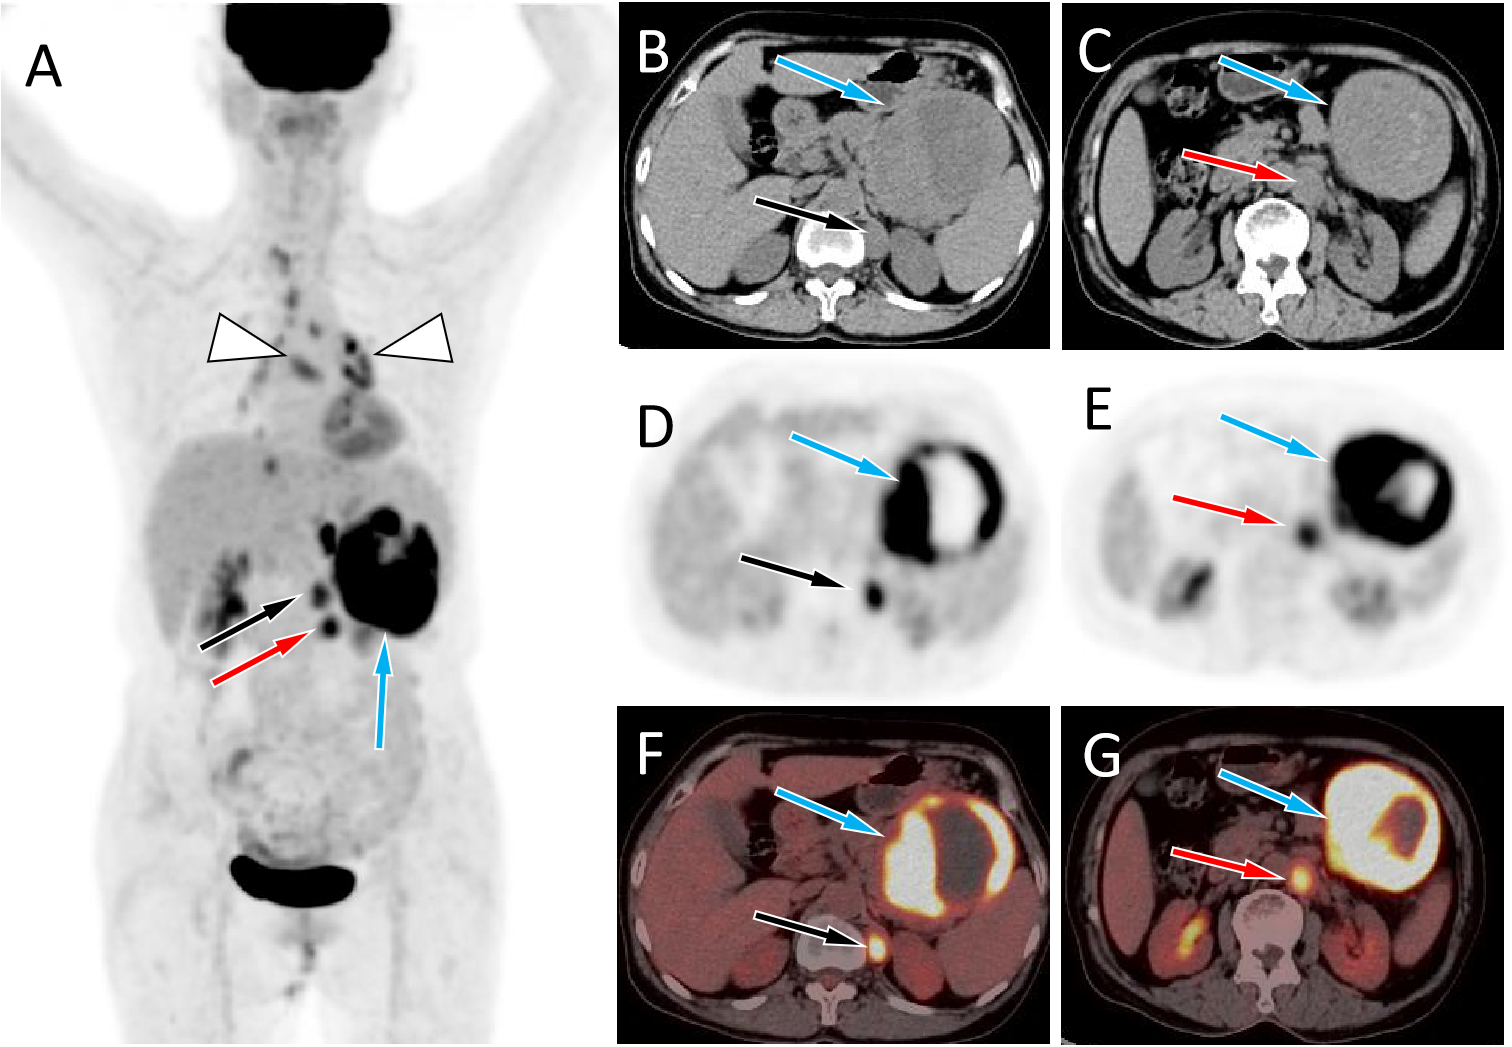

Figure 2

(A) The maximum intensity projection of the PET/CT shows a large tumor with increased 18F-FDG uptake in the left mid-upper abdomen (blue arrow) and two nodules with increased FDG uptake on its inner side (black and red arrows). Moreover, non-specific inflammatory lymph node uptake of 18F-FDG was observed in the mediastinum and hilar area (triangular arrows). Axial images B, C, CT; D, E, PET; F, G, PET/CT fusion images) showed the corresponding large tumor at the tail of the pancreas (blue arrows) and the corresponding two nodules at the left foot of the diaphragm (black and red arrows) and retroperitoneum (red arrows), with increased 18F-FDG uptake.

A 67-year-old female patient with no obvious cause of left upper abdominal pain for 3 days was treated at her local county hospital. Laboratory examination showed elevated white blood cells (14.38×109/L, reference range: 3.5–10×109/L), increased hypersensitivity C-reactive protein (237.9 mg/L, reference range: 0–8 mg/L), normal serum amylase levels, and unrelieved left abdominal pain after the local hospital administered anti-inflammatory treatment for suspected acute peritonitis. The patient subsequently visited our hospital for further diagnosis and treatment. Physical examination revealed no other positive signs except tenderness in the patient’s left upper abdomen. Tumor markers of the digestive system, including ferritin, carbohydrate antigen (CA)-724, CA-199, alpha-fetoprotein, and carcinoembryonic antigen, were all within normal reference values. Abdominal computed tomography (CT) and magnetic resonance imaging (MRI) revealed a large cystic solid mass lesion in the tail of the pancreas, without clear boundaries with the surrounding gastric wall and intestines. It was suspected to be a malignant tumor (Figure 1). To further assess the presence of distant metastases, the patient underwent fluorine-18-fluorodeoxyglucose positron emission tomography (18F-FDG PET)/CT, which showed increased 18F-FDG uptake in the peripheral part of the corresponding lesion. Moreover, multiple nodules with increased FDG uptake were observed in the left diaphragm foot and retroperitoneum (Figure 2). Based on these imaging findings, the patient was suspected to have pancreatic malignancy with retroperitoneal and left diaphragmatic foot lymph node metastases and underwent tumor tissue resection and lymph node dissection. The resected tumor tissue was sent for pathological examination. Hematoxylin and eosin (H&E) staining revealed small round tumor cells, with eosinophilic particles visible in the cytoplasm, and deeply stained nuclei showing mitotic images (Figure 3). Immunohistochemistry (IHC) results showed that the tumor cells positively expressed CD34, CD43, myeloperoxidase (MPO), and P53, and negatively expressed CD117, CD138, CD20, CD3, CD34, CD5, and cytokeratin (CK). Based on these histopathological findings, the patient was diagnosed with pancreatic MS. Owing to the high malignancy of MS, the patient received chemotherapy with cyclophosphamide, doxorubicin, vincristine, and dexamethasone after surgery. Unfortunately, CT examination of the patient 5 months after surgery revealed liver metastases (Figure S1), and the patient was subsequently lost to follow-up.

Imaging examinations, including CT, MRI, and 18F-FDG PET/CT, are essential and helpful for determining the correct preoperative diagnosis and establishing treatment plans. However, there are currently very few reports on the imaging findings of pancreatic MS. Pancreatic MS appears as a homogeneous slightly hypodense or isodense mass on non-contrast-enhanced CT and is prone to cystic change when the mass volume is large (12, 14, 15). On contrast-enhanced CT, it appears as a mild enhancement (4, 8, 9). There are only a few literature reports on the MRI signs of pancreatic MS, which include a slightly lower signal on T1WI, equal or slightly higher signal on T2WI, and limited diffusion on DWI (4, 10). On contrast-enhanced T1WI, MS showed uniform enhancement, with a degree of enhancement similar to that of skeletal muscle (16). MS tumor tissues have a high degree of malignancy and high levels of metabolism; therefore, PET/CT can localize the tumors with an increased 18F-FDG uptake (4, 6, 10, 14). Our patient showed a large slightly hypodense soft tissue mass with cystic changes on CT, and slightly longer T1 and T2 signals on MRI with mild enhancement. On PET/CT, the mass showed a high concentration of 18F-FDG, with an SUVmax of 10.4, which is consistent with previous reports. Pancreatic MS needs to be differentiated from other tumors, including pancreatic cancer, serous cystadenoma, and solid pseudopapillary tumors, according to its clinical and imaging characteristics. Pancreatic cancer usually presents as a slightly enhanced, equal-, or slightly low-density mass. However, CA199, a serum tumor marker, is usually positive in MS. Pancreatic serous cystadenoma often presents as a multilocular cystic mass, and the cystic lesions are divided into several cystic cavities by thin fibrous septa. Fibrous septa can aggregate into central scars with calcifications, which are characteristic manifestations of serous cystadenoma (17). Solid pseudopapillary tumors of the pancreas are more common in young women, are usually located in the body and tail of the pancreas, and exhibit progressive enhancement on contrast-enhanced CT or MRI as a relatively specific characteristic (18).